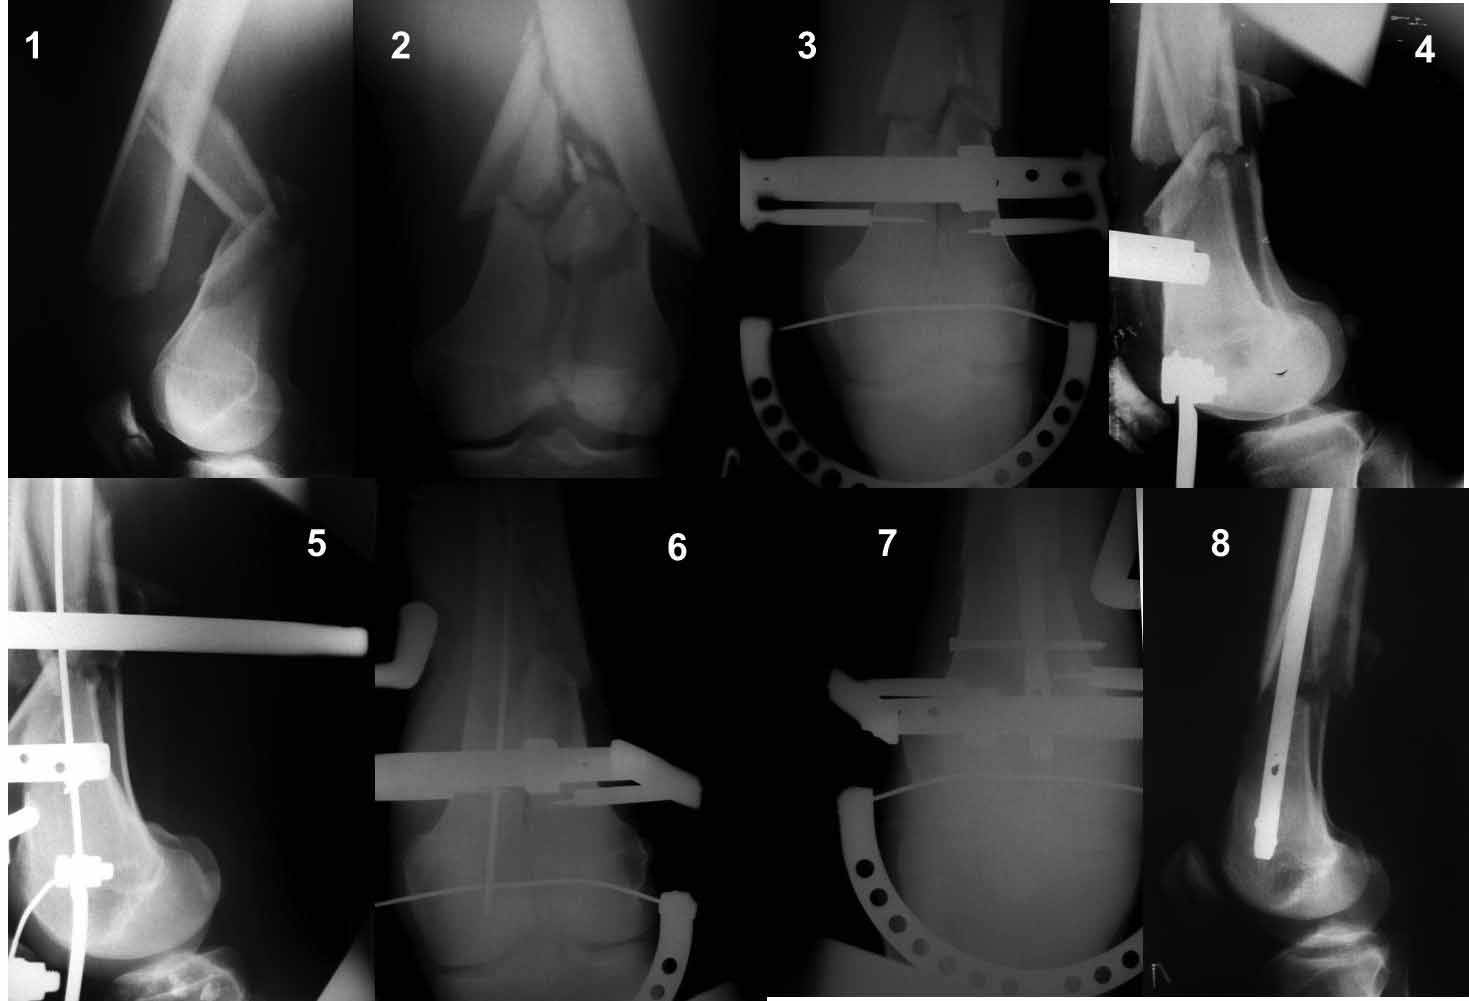

Ну зачем же так. Всё-таки считается "золотым стандартом". Во вложенном файле коллаж из сохранившихся фотографий одной из операций. Всё сделано закрыто и без ЭОПа.

|